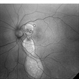

- Central Serous Chorioretinopathy (CSR)

- Fundus photograph of RE showing Central Serous Chorioretinopathy.